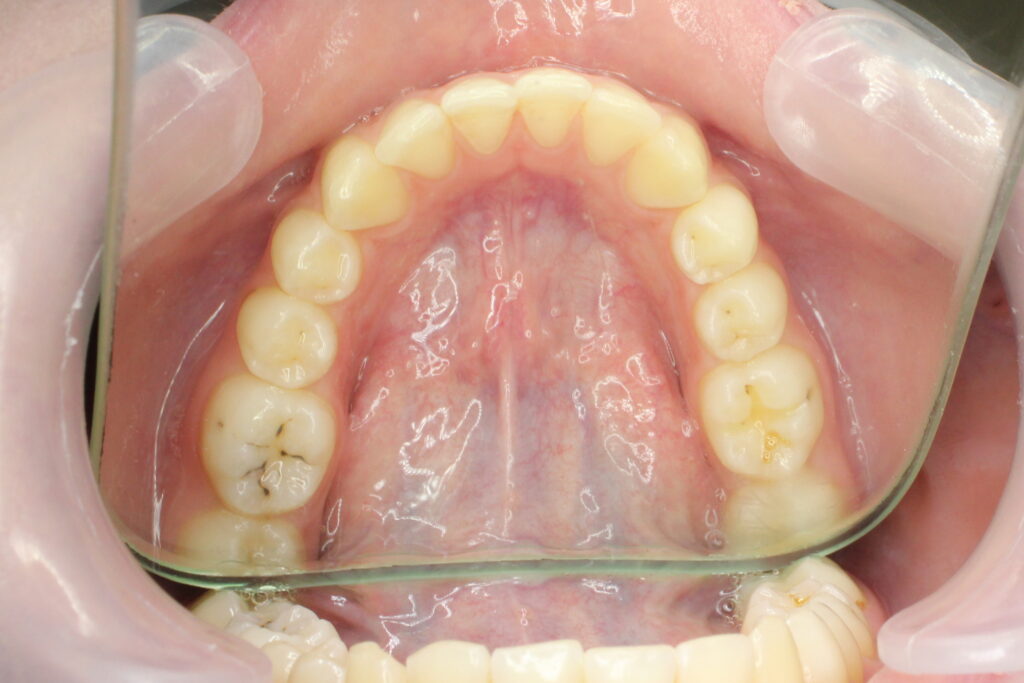

Ситуация до лечения

Диагноз: дистальный прикус, сужение, удлинение верхнего зубного ряда, скученность фронтальной группы зубов на нижней челюсти. Лечение проводилось самолигирующей брекет-системой Damon Q, срок лечения составил 2 года и 2 месяца.

Ситуация до лечения брекетами